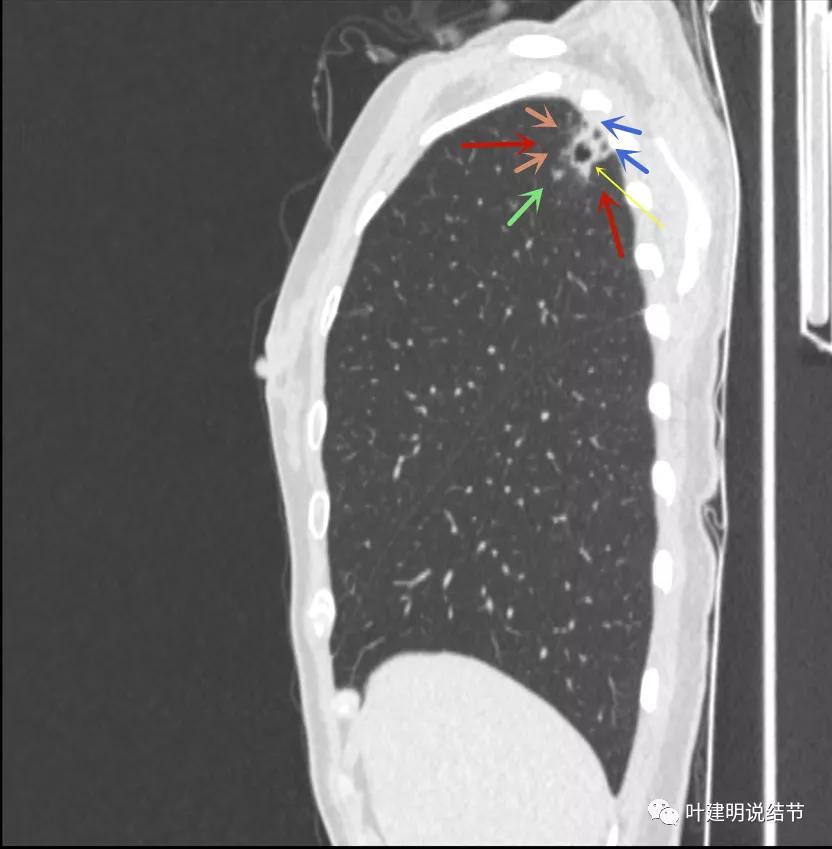

病灶较散,有磨玻璃影,但磨玻璃的边缘模糊不清(砖色箭头),囊壁密度过高(粉色箭头),毛刺样的结构偏长,空洞内壁较光滑,有卫星灶(绿色箭头)

病灶邻近胸膜增厚明显(蓝色箭头);病灶似三角形,边缘平直(桔色箭头);有磨玻璃淡且散,边缘不清(砖色箭头);有卫星病灶(绿色箭头)

有卫星灶,且条索状(绿色箭头),囊壁密度过高(粉色箭头);有空腔征(黄色箭头)